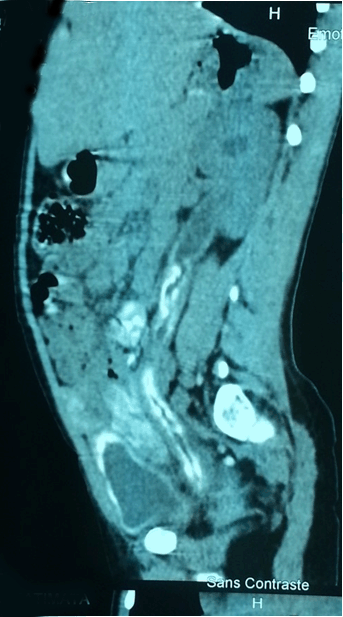

At dermatological examination, the patient had an itchy swelling of the big labia, small labia, clitoris, and groin folds of the aspect of papulo-fibrous and nodular on palpation (Figure 1). No abnormalities found in the gastrointestinal examination. The rest of the examination was unremarkable. Diagnostic hypotheses were discussed: cutaneous calcinosis, vulvar tuberculosis, cutaneous sarcoidosis and cutaneous schistosomiasis. The blood count showed anemia (hemoglobin 8 g/dl), normocytic (MCV 80.9 fl), normocytic (MCHC 33.2 g/dl) and hypereosinophilia 21.1%. The erythrocyte sedimentation rate was accelerated, CRP was positive. The parasitological examination of urine was normal. The skin histology showing under acanthotic epidermis, inflammatory granulomatous reaction around bilharzia viable eggs of Schistosoma haematobium, grouped into small clusters of a few elements surrounded by lymphocytes plasma cells, eosinophil's polynuclear, histiocytes, épithélo?des and multi-nucleated. Images of microabscesses were visible around Schistosoma eggs in entering the squamous epithelium to the keratin layer (Figure 2) and (Figure 3). The diagnosis of vulvar skin bilharzia was set. The abdominal pelvic ultra sound showed a bilateral ureteral hydronephrosis, uroscanner without product injection noted an irregular parietal calcification of the bladder, ureters under pyelic, urethra, rectum, sigmoid colon and left with segmental dilatation of the ureters and expansions moderate bilateral pelvicalyceal (Figure 4).

Figure 4: Sagittal computed tomography urography without injection of product showing an irregular parietal calcification of the bladder, ureter under pyelic, sigmoid with segmental dilatation of the ureter and pelvicalyceal expansion.

Cutaneous schistosomiasis may be associated with obstructive consequences of urogenital apparatus which result in a ureteral hydronephrosis in some cases, hence the importance of abdominal ultrasound. These complications were described by Garba in Niger and N'guessan in Ivory Coast (West Africa) [15] [16]. They found about 329 students, 2.74% of cases of dilatation urinary tract and bladder lesions of 40.43%; among bladder lesions, the wall thickening was noted in 14.89%. Computed tomography (CT) scan without injection is the preferred exam to confirm the calcification of the bladder, ureter and urinary tract [17]. Due to its cost in our context of limited resources, the application is not systematic. In our case, it helped to highlight the digestive and urinary calcifications.